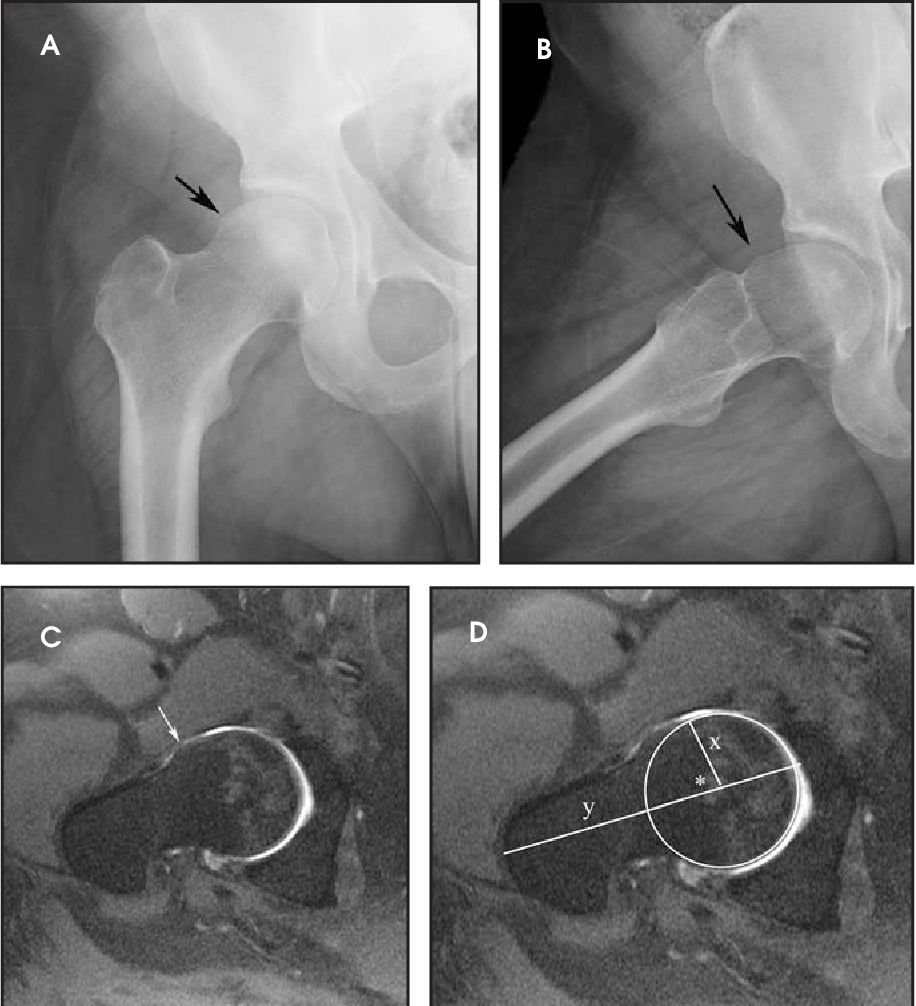

1.CAM-тип

Нарост (бугорок) или утолщение на бедренной шейке/основания головки, что делает её не идеально сферической. При сгибании/вращении бедра это утолщение «входит» в вертлужную впадину и травмирует край впадины или губу.

- Рентгенография: выявление морфологии, утолщения, изменения формы.

- МРТ / МР-артрография: оценка состояния хряща, губы, мягких тканей, наличие сопутствующих повреждений.